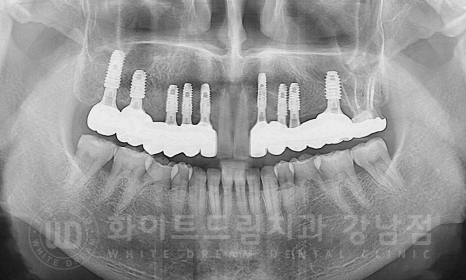

골질도 나쁘지 않았고 초기 고정력이 안정적으로 나와 총 8개의 임플란트를 발치 후 당일 식립하고, GBR(골 유도 재생술),

2차 수술까지 한 번에 진행했습니다.

20.06.30 상악 임플란트 8개 식립 & GBR 시행

모든 임플란트 수술이 완료되었고, 이제 임플란트와 잇몸뼈가 잘 유착되면 보철을 세팅하면 치료는 종결됩니다.

그래서 최종 보철을 하나로 묶지 않고 나누어 보철을 제작해 드렸고

주변 치아색과 굉장히 자연스럽고, 원래 있던 치아처럼 자연스럽게 보철이 제작되었습니다.